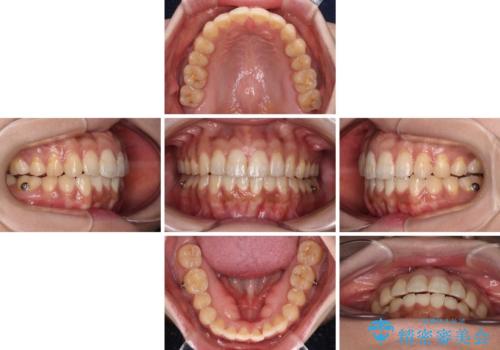

舌突出癖改善のためのトレーニングを行いながら、インビザラインにて矯正治療を行うこととしました。

舌のトレーニングをしっかりと行っていただき、上下前歯をしっかりと接触させることができました。

咬合力が強いため、治療途中に奥歯が咬み合わない期間が続きましたが、上下の奥歯でゴムかけを行っていただき、違和感なく咬み合うように仕上げることができました。